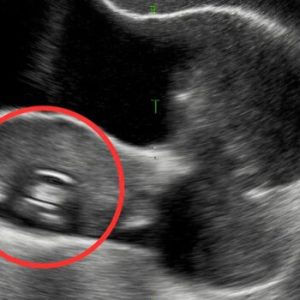

A high-risk pregnancy, our journey to welcome our son was unforgettable and amazing.

From the time I was a teenager, motherhood was never just a distant possibility—it was a future I could picture with surprising clarity. My husband and I were high school sweethearts, the kind…